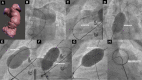

Case summary: Here, we describe a case of a patient who had surgical fallot repair with chronic heart failure. Investigations found severe biventricular dysfunction and enlargement due to chronic pulmonary regurgitation. The right ventricle outflow tract was tortuous and large with a diameter of 35 mm. Percutaneous pulmonary valve implantation (PPVI) was done after a challenging pre-stenting. A 32 mm Myval valve over-sized to 35 mm was used for PPVI, which yielded a good result.

Discussion: A 32 mm Myval valve is effective at extending the possibilities of PPVI in a large and tortuous right ventricle outflow tract not accessible for the other valves.